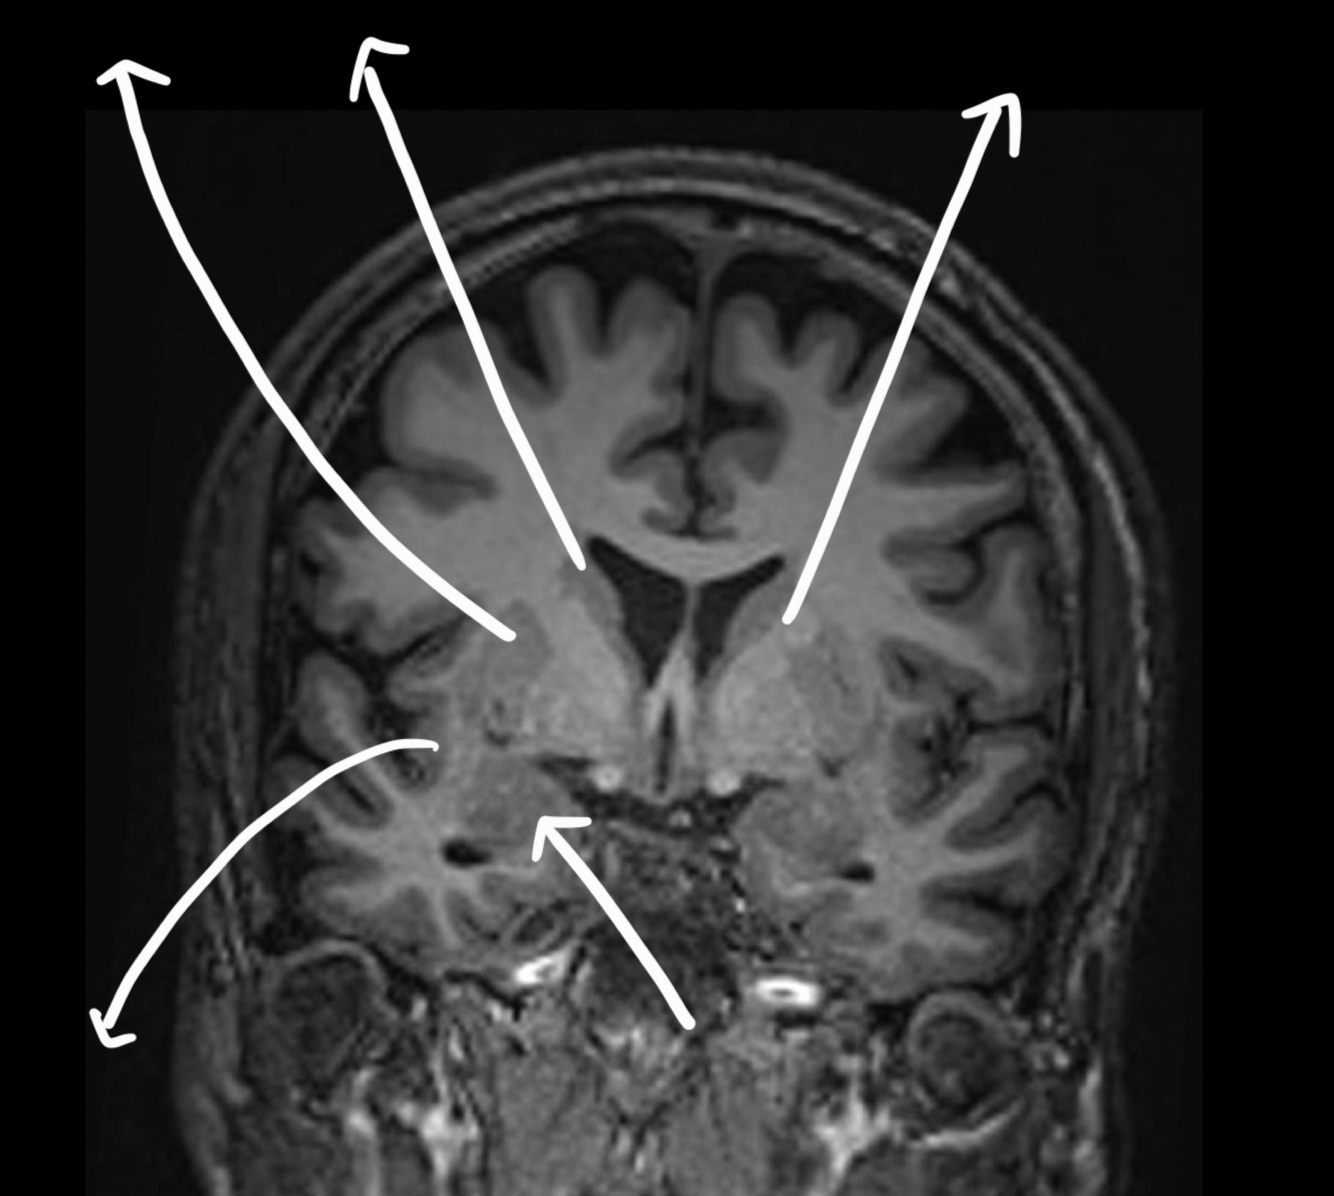

What can we see in this image?

A

A fetal MRI for CNS evaluation